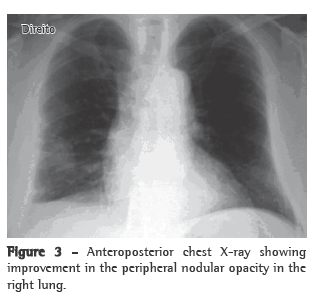

With treatment, the patient presented improvement of the clinical manifestations and the pulmonary alterations resolved (Figure 3).